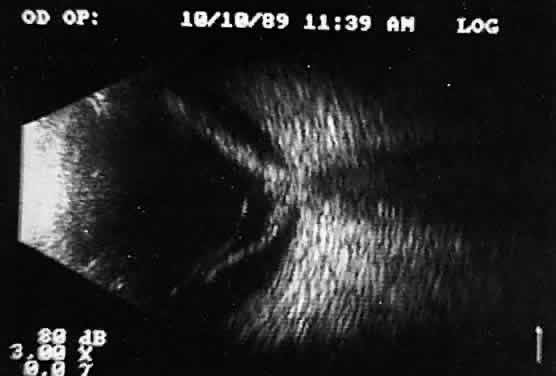

Real time refers to the display of motion or movement during B-scan imaging. This capability is one of the greatest advantages of B-scan. Differences in mobility of a variety of movable intraocular abnormalities can be easily detected. For example, the rapid movement of vitreous hemorrhage is usually easy to appreciate and differentiate from the slower, undulating movements of a recent, rhegmatogenous retinal detachment. On occasion, movement of intraocular structures can be used for detecting abnormalities that lie immediately behind vitreous opacification and may be seen only when the vitreous opacities are moved away from the ocular wall, set in motion by command voluntary movements of the patient's globe (Fig. 5). Gray scale refers to the variable gray tone of display screen echoes. Strong returning signals (echoes) appear white, whereas weaker reflections are seen as gray, the shade depending on echo strength. Examples of strong reflectors of sound include retinal tissue, sclera, and calcifications of any type (Fig. 6). Weaker echoes from clotted or clumped cells within the vitreous are usually easy to differentiate from the stronger reflectors of sound (Fig. 7). Grading of echo strength may be performed only when the examining ultrasound beam is perpendicular to the object of interest, ensuring the strongest possible reflections. However, in the world of ultrasound interpretation, there are many exception to the rules. Tissues that are usually mild reflectors of sound, such as hemorrhage, can at times appear quite strong, especially in complex or multiple pattern disorders, as frequently occur in severe ocular trauma. These apparent inconsistencies often cause misinterpretation by the novice. With experience obtained by multiple examinations, careful follow-up, and clinical correlation whenever possible, diagnostic acumen rapidly improves.

Fig. 5. Contact B-scans. A. Heavy formed vitreous hemorrhage obscuring choroidal mass. B. Voluntary movement of the globe causes the formed vitreous to shift, permitting easy detection of the ocular wall mass.